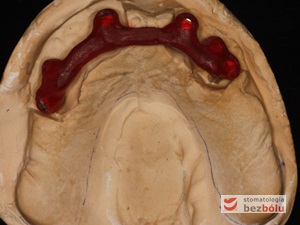

Gotowy most z maską dziąsłową - zastosowanie maski dziąsłowej uzasadnione długością zębów

Gotowy most z maską dziąsłową – zastosowanie maski dziąsłowej uzasadnione długością zębów